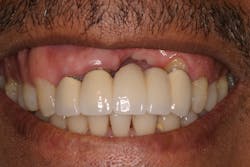

Reduction in quantity and quality of bone can also compromise functional and esthetic outcomes of both implants and fixed bridge restorations (figures 3 and 3a).

• Site development to increase hard and soft tissue for pontic sites in fixed bridge prosthetics (figures 4–4e)